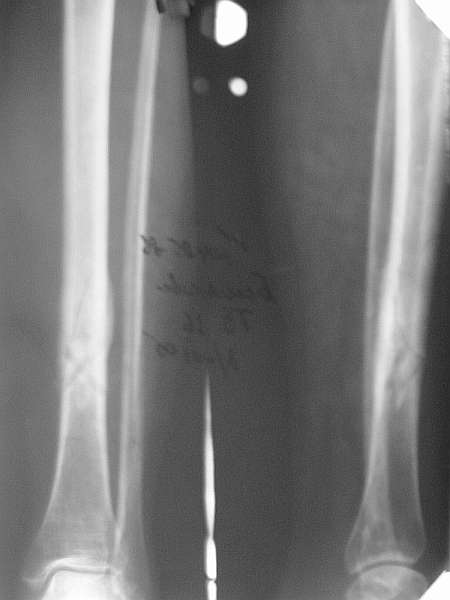

Типичный косо-спиральный перелом голени с низкой энергией, большеберцовая внизу, а сверху малоберцовая, и применение интрафрагментарного компрессионного шурупа можно оправдать, когда для

фиксации перелома выбран метод открытой фиксации пластинами, где пластина после стабилизации и компрессии перелома действует как нейтрализующая сила.

Из-за убедительных преимуществ перед другими методами, при лечении закрытых диафизарных переломов голени “золотым стандартом” считается применения метода закрытой репозиции с фиксацией интрамедуллярным штифтом, проксимальным и дистальным блокированием. Тенденция сегодняшнего дня - это перевод в окончательную фазу фиксации, в

Без установки межфрагментарного шурупа, предпочителями отечественного метода Илизарова, дежурным аппаратом из двух колец при поступлении в приемном покое и на следуюший день двумя дополнительными спицами с напайкой за пределы фокуса решили бы проблему в два счета.

Такие изолированные (low energy trauma) переломы голени лечатся также гипсом, поэтапным консервативным методом Sarmiento, поэтому трудно согласиться с принятии метода, дать ему "право на жизнь" как стандарта для лечении при изолированных переломов голени.